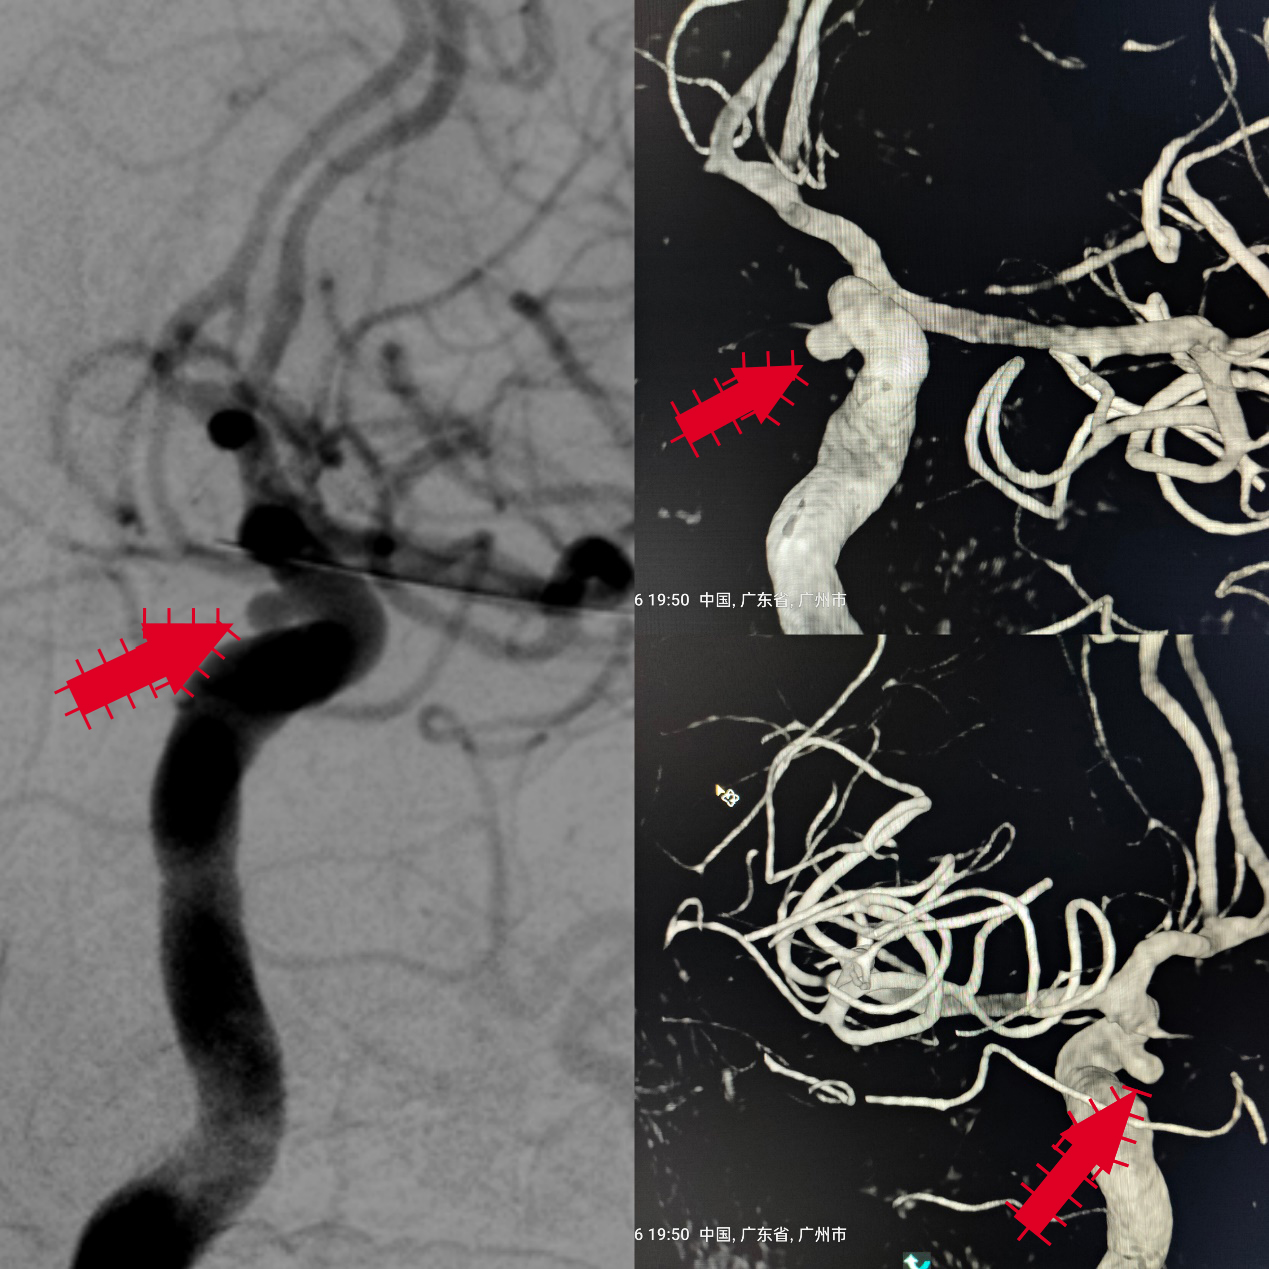

该患者是一名中年男性,因周围性面神经麻痹在我神经内科一区住院,住院期间完善头颅MRA提示可疑左侧颈内动脉眼动脉段动脉瘤(图1),脑血管造影及3D图像重建明确了左侧颈内动脉眼动脉段动脉瘤形态,位置及大小(图2)。

图1

图2